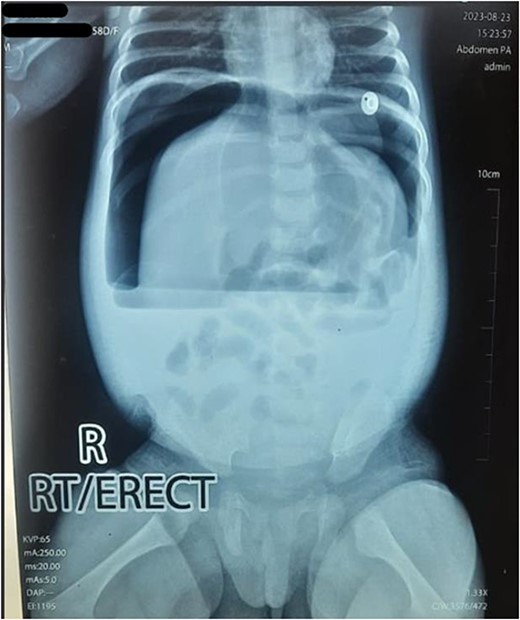

Upon arrival, we conducted a comprehensive medical history review and relevant physical examinations. The baby, delivered via Cesarean section due to fetal distress, had no major health issues except for her mother’s gestational diabetes and a second-trimester urinary tract infection, both managed conservatively. Initial examination indicated signs of dehydration, including a high heart rate, elevated respiratory rate, and 97% oxygen saturation with oxygen support. Abdominal examination revealed distention, visible veins, firmness, and absent bowel sounds. Respiratory and cardiovascular examinations were normal. An erect abdominal X-ray revealed pathological free gas under the right dome of the diaphragm, strongly suggesting a hollow viscus perforation as shown in Fig. 2. Routine blood tests were normal, with a slightly elevated CRP level at 9.5 mg/dl.

Erect X-ray showing pathological free gas under bilateral dome of diaphragm.